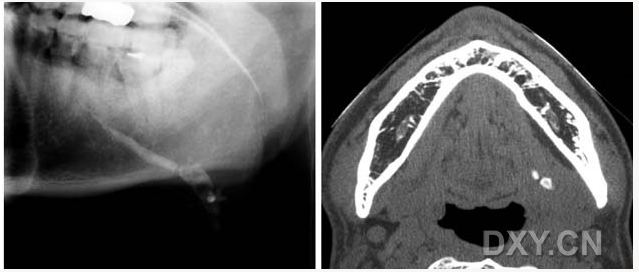

骨肉瘤

涎石病

頜骨纖維性結(jié)構(gòu)不良癥